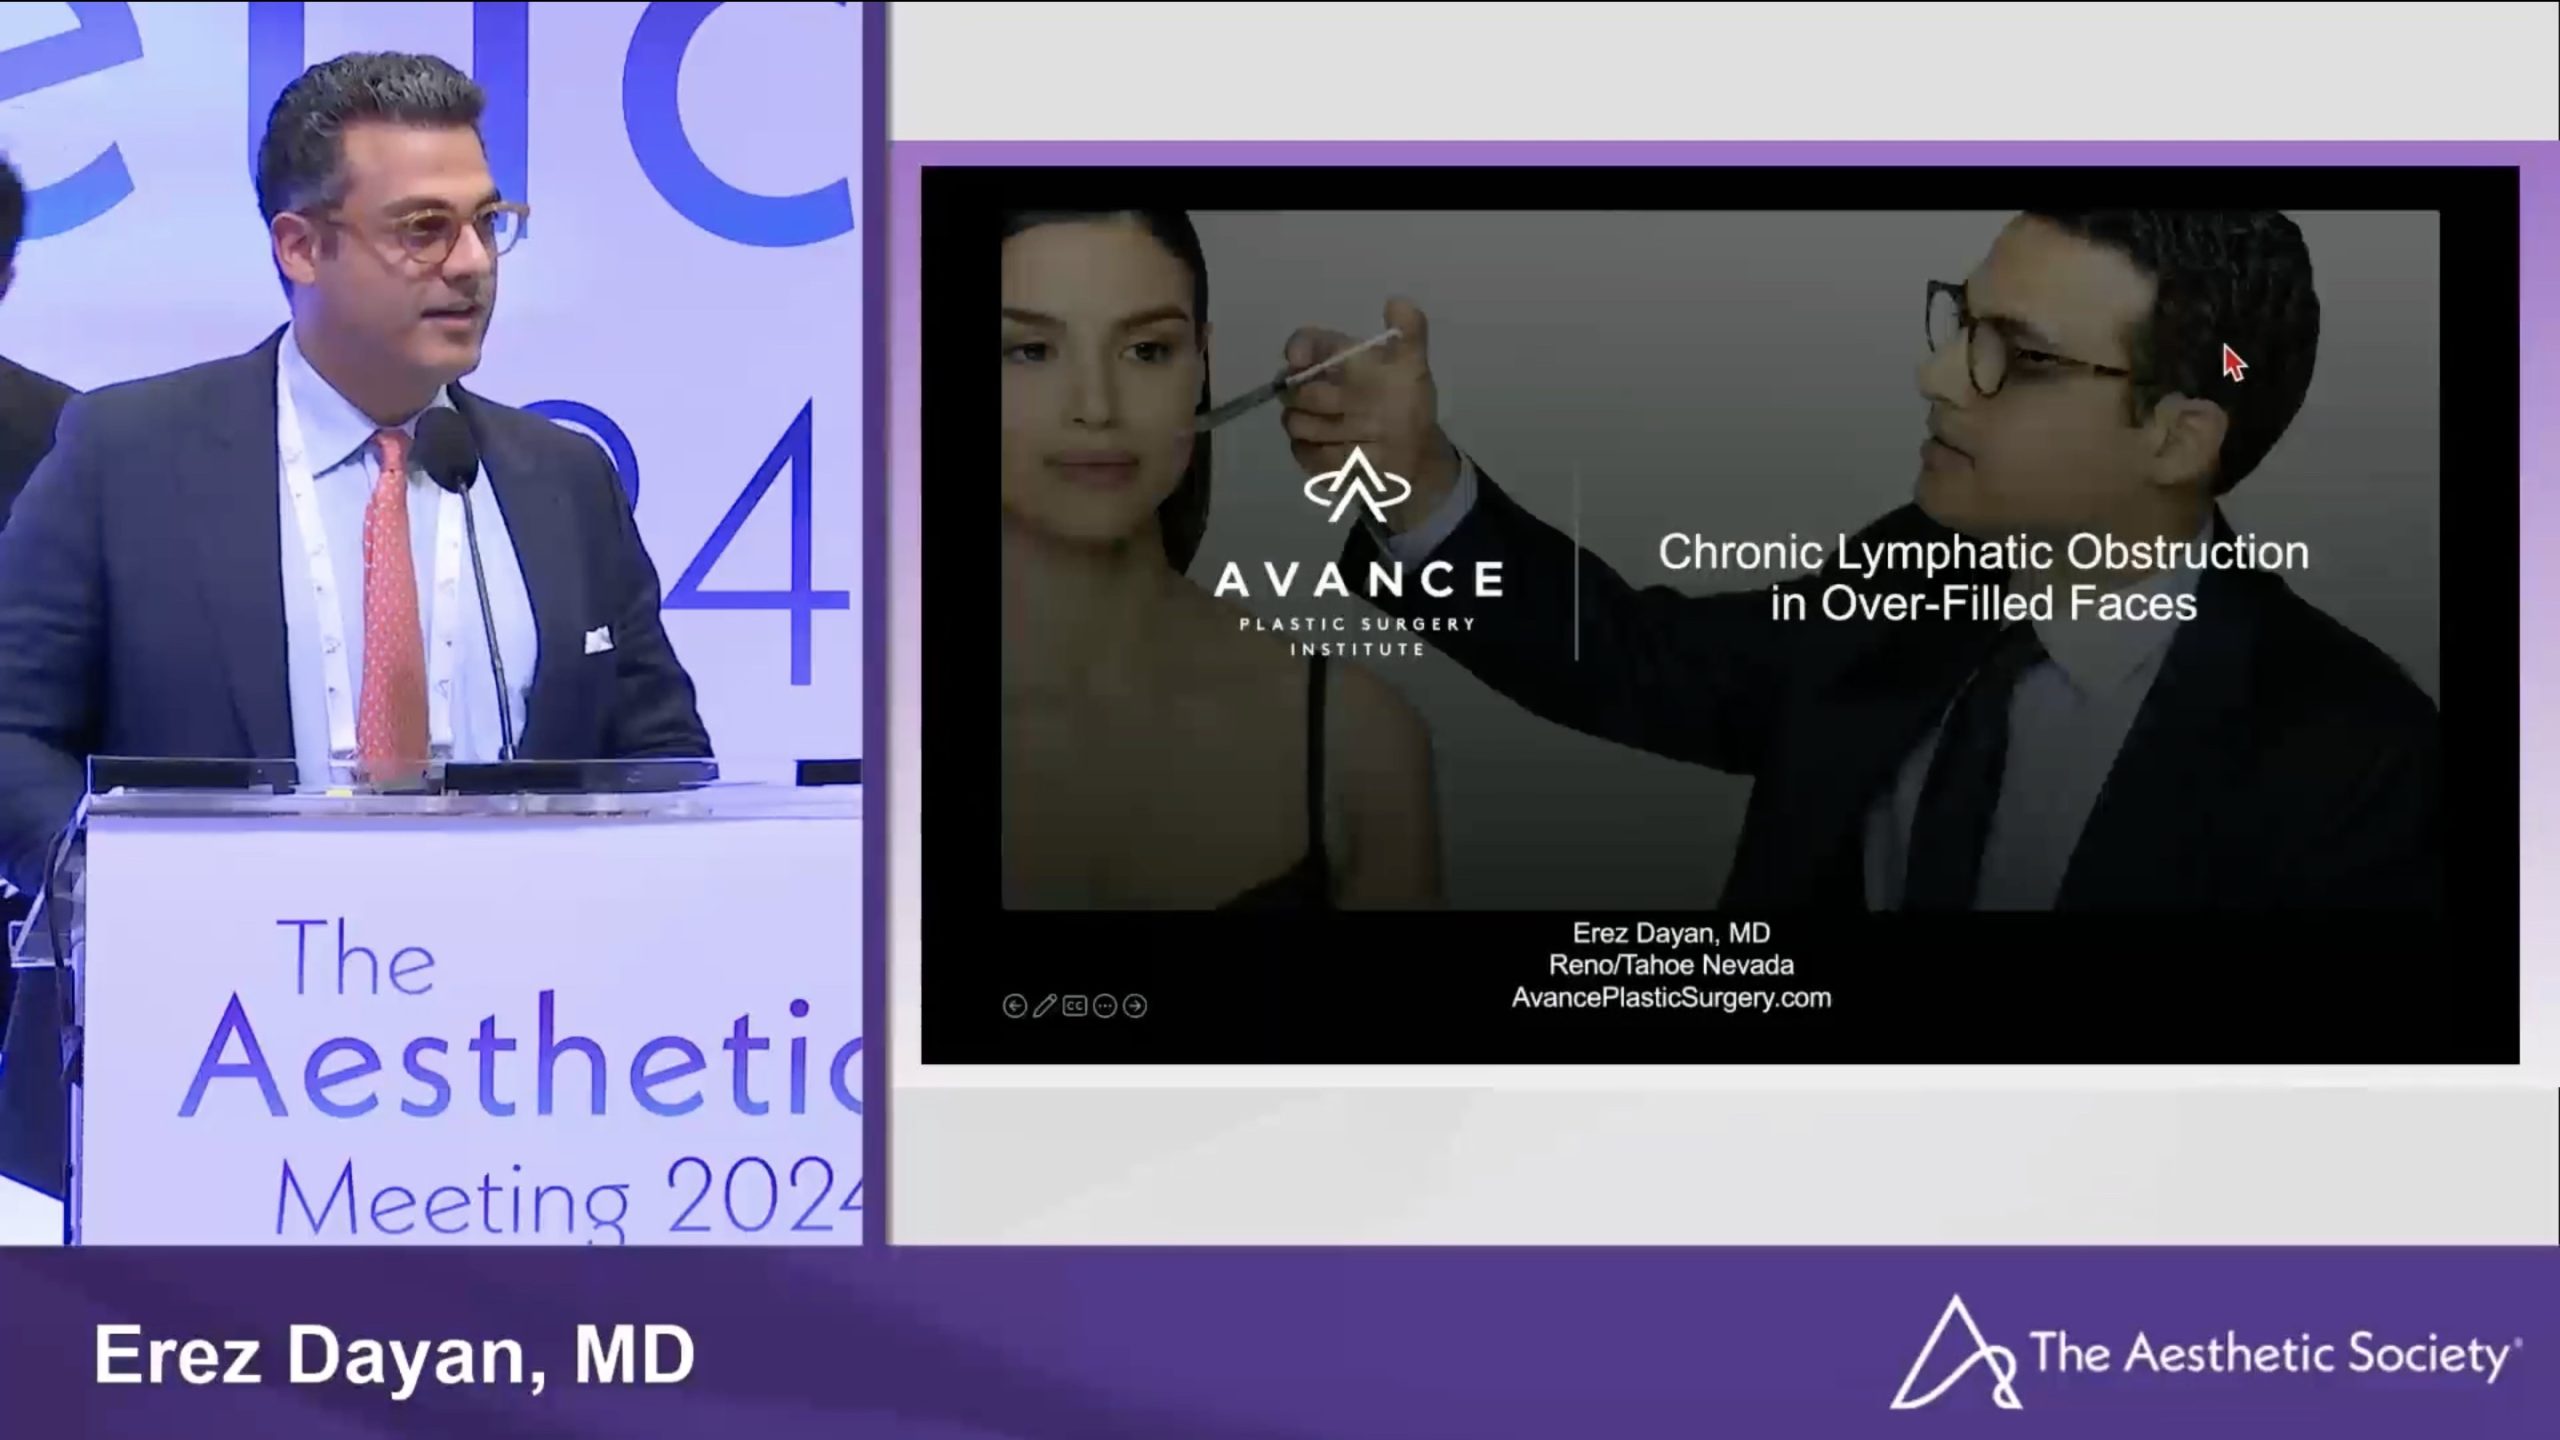

Dr. Erez Dayan presents a breakthrough approach using Morpheus8 RF to address Post-Hyaluronic Acid Recurrent Eyelid Edema (PHAREE) and lymphatic obstruction.

Justin Karlin, MD, MS, Neil Vranis, MD, Erez Dayan, MD & Kami Parsa, MD

Aesthetic Surgery Journal Open Forum